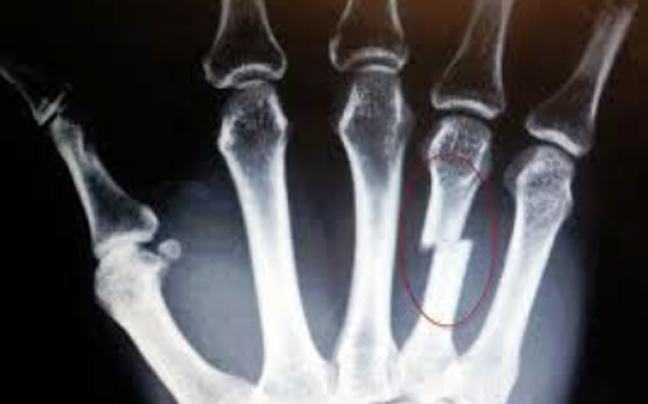

Τα μετακάρπια είναι τα κόκαλα που προηγούνται των δακτύλων και σχηματίζουν το έδαφος της παλάμης. Υφίστανται κατάγματα από άμεση πλήξη, σε πτώση ή από σύνθλιψη.

Mε τον δείκτη ανευρίσκουμε το σημείο ευαισθησίας. Με την πίεση προκαλείται «κριγμός» κι οξύς πόνος. Η διάγνωση επιβεβαιώνεται με ακτινογραφία όταν υπάρχει.

Tα κατάγματα των μετακαρπίων σήμερα χειρουργούνται εύκολα. Όμως εάν ακινητοποιηθεί το κάταγμα με μεταλλικό νάρθηκα (zimmer) ή σε θέση γροθιάς το αποτέλεσμα θα είναι επίσης εξίσου ικανοποιητικό.